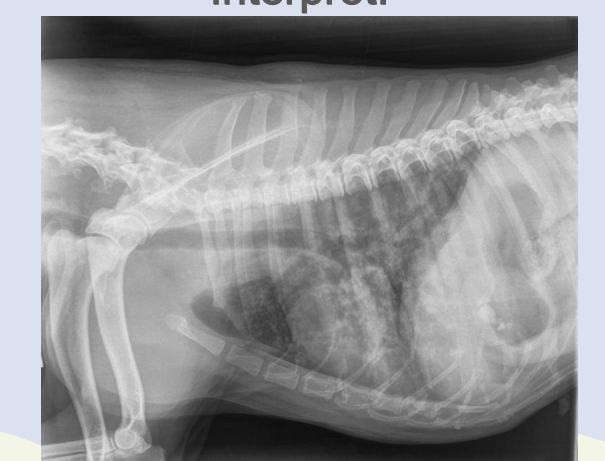

Interstitial pattern

aorta and vena cava is blurry